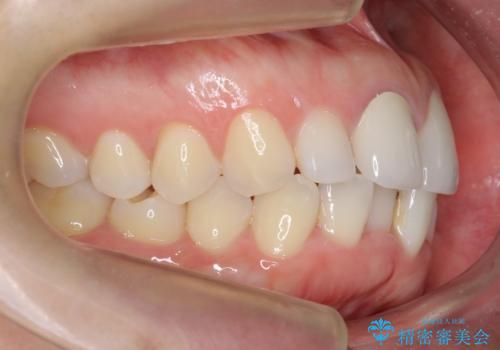

銀歯と、プラスチックをセラミックにかえました。

- 合計 19.8万円 右上7:セラミックインレー 7万円、右上6:ジルコニアクラウン10万円、仮歯1万円費用は治療当時の料金となります

右上6番は詰め物が大きく、インレーではなくクラウンとしました。